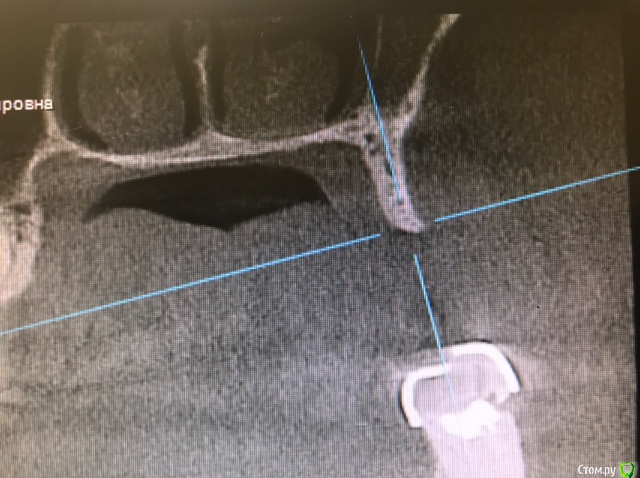

колесников Опубликовано 16 марта, 2019 Автор Поделиться Опубликовано 16 марта, 2019 (изменено) Ну как бы тут все очевидно. Слева стала костью,справа нет. Но должен вам отметить,что даже в случае неудачи (как кажется)потери нет. Задача стояла не увеличить объём для имплантации или укрыть Имплант,а снять напряжение с вершины гребня и дать созреть десне. Имплант в нативной кости,он интегрирован,десна успела созреть за это время,возможно будет не так объёмно как хотелось бы,но у меня в запасе этап раскрытия ,фдм зарос ,есть с чем поработать. Все что не интегрировалось ,лизируется самостоятельно,выскребать ничего не нужно,ещё подождать. Изменено 16 марта, 2019 пользователем колесников Ссылка на комментарий